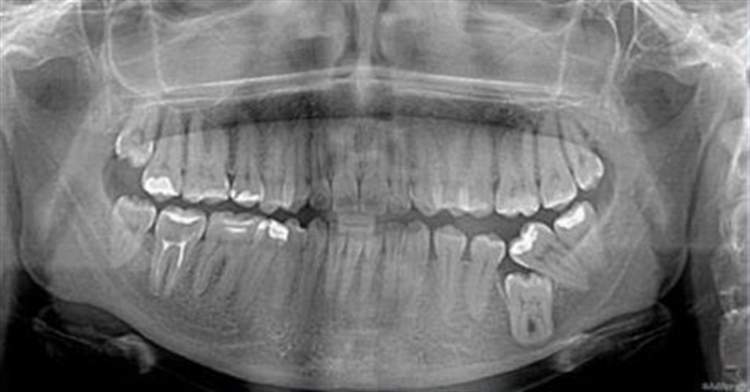

І хочеться показати вам ось таке:

Це зубки однієї дуже популярної телеведучої нашого міста. Ім’я вказувати не буду. На момент виконання рентгенограми дівчині було 26 років, вона регулярно звертається до нас на «профчистки» і лікування. У неї все добре.